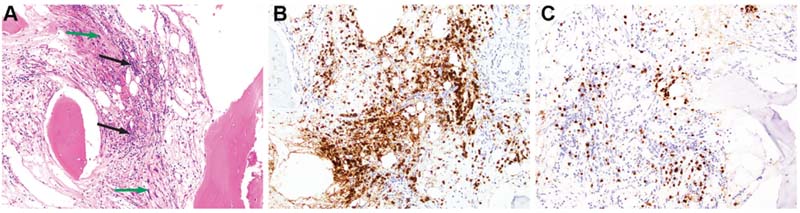

Following the molecular results, re-review of the sacrum biopsy revealed, in addition to the metastatic sarcoma, patchy infiltrates of small lymphocytes with slightly irregular nuclei, mature chromatin, and occasional intermixed plasma cells, present within the bone marrow (Fig. 2A). Subsequent immunohistochemistry showed that most of the lymphocytes were CD20+ PAX5+ B cells (Fig. 2B), which were CD5 negative. CD3 highlighted fewer interspersed small T cells (Fig. 2C). MUM1 was positive in a few intermixed plasma cells, which appeared polytypic for kappa and lambda light chains by chromogenic in situ hybridization; only rare plasma cells were IgM positive. Overall, the CD20+ B-cell infiltrates occupied 10 to 15 percent of the intertrabecular marrow space.